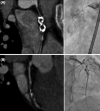

Sudden cardiac arrest (SCA) is an uncommon but devastating event among young adults. While inherited cardiomyopathies and channelopathies represent an important proportion of sudden deaths, coronary artery disease remains a significant contributor in this age group. ECG findings are essential to guide the first steps of diagnostic work-up of SCA, but sometimes can overlap between different etiologies. In this article we present a 16-year-old female who experienced SCA during vigorous swimming whose ECG was compatible with long QT syndrome. However, evaluation of the coronary anatomy provided the diagnosis of Kawasaki disease.